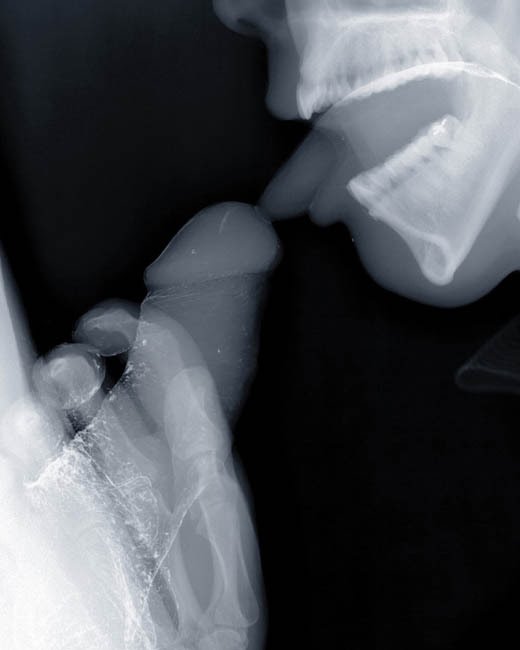

MudamSérie 9 muses (2001) : série de vitraux réalisés avec des plaques d'imagerie médicale aux rayons X eux-mêmes « X » puisqu'il s'agit de scènes pornographiques (fellation, coït).

Lick 2, 2000.

Pipe 2, 2001

Blow